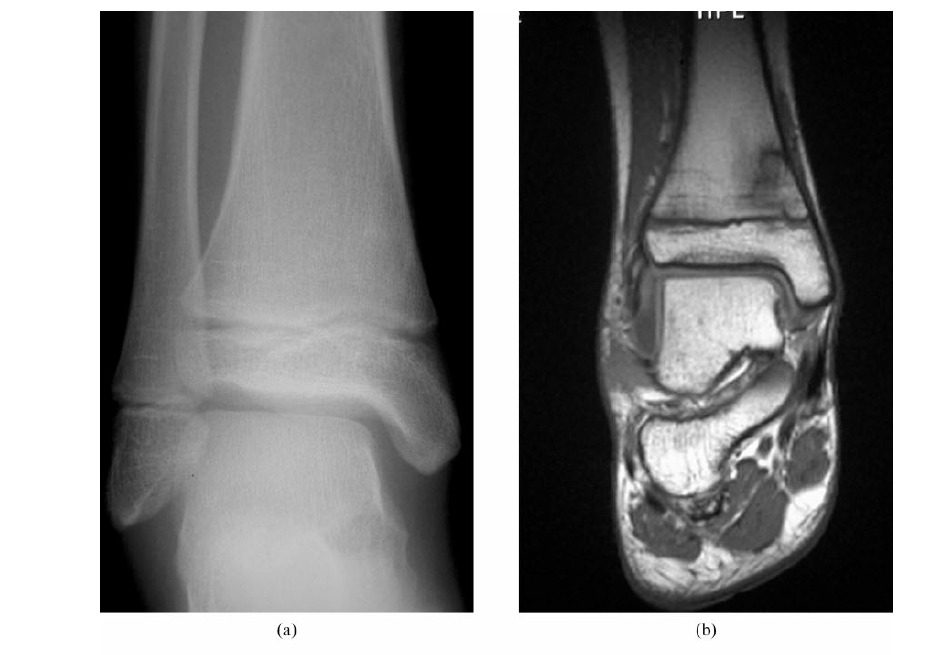

# Plain films are useful as an initial screen test for diffuse ankle and foot pain.

# MRI is the most suitable technique for global assessment of bone and soft tissues for persistent pain following injury.